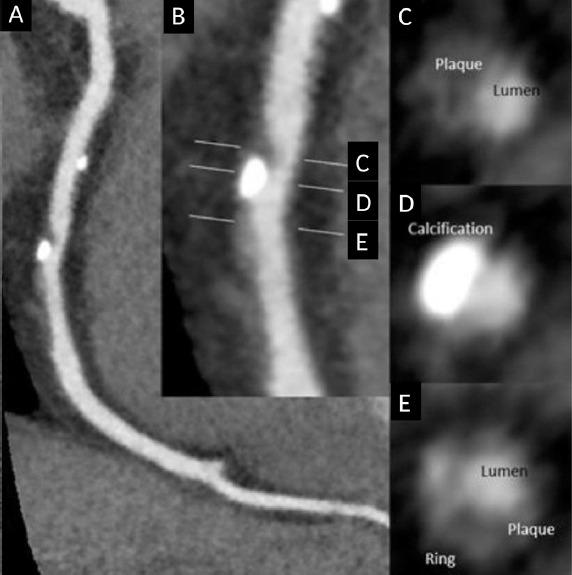

近年来,心脏CT技术的快速发展提高了图像质量,并减少了患者的辐射暴露。此外,大型队列试验的关键见解有助于将心血管疾病风险描述为总体冠状动脉斑块负荷和单个斑块形态外观的函数。CT衍生的血流储备分数的出现有望在一种检查方式中建立解剖学和功能测试。最近发表了关于CT衍生的血流储备分数对下游治疗和临床结果的短期影响的数据。此外,机器学习是一个越来越多地应用于诊断医学的概念。在未来十年中,机器学习将开始融入心脏CT,并可能对这种检查方式的发展产生切实影响。作者对心脏CT的最新进展进行了广泛的文献综述和全面分析。他们回顾了最近的进展如何影响当前的临床护理以及这种成像方式未来可能的发展方向。